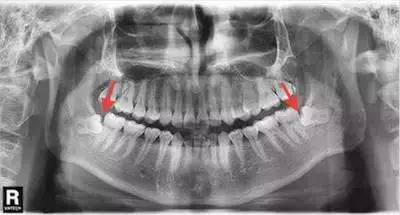

5/ 智齿萌出的方向不正常,也会造成食物易嵌塞在倾斜的空隙里。

智齿造成牙齿经常“卡肉”的,考虑拔除智齿。